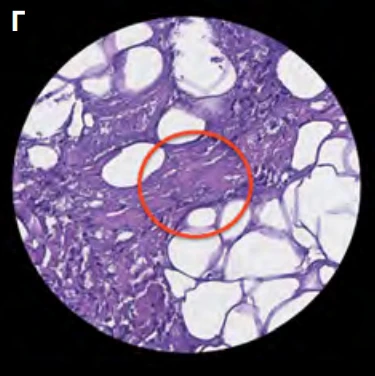

Через 1 нед. и 1 мес. после процедуры Morpheus8 у пациентки были взяты образцы тканей субментальной зоны. Наблюдались следующие структурные изменения состояния жировой ткани и соединительнотканных перемычек:

• через 1 нед. – признаки лизиса адипоцитов;

• через 1 мес. – признаки распада адипоцитов, уменьшение среднего размера адипоцитов на 37,6%, уплотнение и реструктуризация коллагеновых волокон (плотность возросла на 42,4%), более 62% волокон имеют строгую ориентацию по сравнению с исходным состоянием (34%) (рис. 14).

...

Рис. 14. Изменение структуры подкожно-жирового слоя после обработки Morpheus8: А – исходное состояние; Б – через 1 нед. после процедуры; В – через 1 мес. после процедуры; Г – уплотнение и реструктуризация коллагеновых волокон ФСС через 1 мес. после процедуры (материал предоставлен С. Л. Первых).